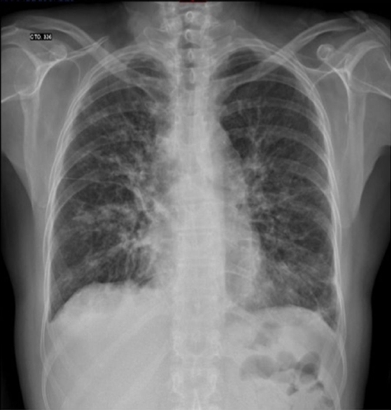

MLG is a female 58 years old with a history of rheumatoid arthritis diagnosed in December 2011 based on elevated rheumatoid factor, erythrocyte sedimentation rate and C-reactive protein, the presence of anticyclic citrullinated peptide antibody (anti-CCP), and bony erosions in the hands. She initially received treatment with immunosuppressors (methotrexate) and later with biological (abatacept) therapy with improvement and remission of the disease. She presented to the emergency room of our institution with a 3 weeks-history of a progressive dyspnea from great to moderate efforts, palpitations, fever (38.8 ◦C), malaise, dry cough and headache. On examination, she was tachycardic (HR: 101/min), with oxygen desaturation (P02 = 70%) and had bibasilar lung rales. The laboratory analysis showed leukocytosis (21.4 × 103/m3) and mild anemia (Hb – 12.7 g/dL and Htc – 40%). Blood cultures were negative. The chest computed tomography showed areas of bilateral alveolar occupation in relation to acute inflammatory process without pleural effusion. The transthoracic bidimensional (Fig. 1A–F) and three-dimensional echocardiogram revealed nodular thickening on the both mitral leaflets and in the subvalvular apparatus of the mitral valve without mitral regurgitation (Fig. 2A and B), small nodules in the aortic leaflets (Fig. 3A and prominent nodules on the tricuspid valve with mild tricuspid regurgitation (Fig. 3B), mild pulmonary hypertension, left ventricular diastolic dysfunction type I and normal left ventricular systolic function. The patient was treated with intravenous steroids and broad spectrum antibiotics with clinical improvement, but without changes in the valvular lesions. Actually she is in NYHA functional class I and the chest radiograph after the resolution of infectious process showed interstitial lung bilateral thickening and reticulonodular parahiliar and basal pattern, the left cardiac profile is abnormal and the aorta unrolled (Fig. 4).

Figure 4 Chest radiograph showing cardiac silhouette of normal size and position, but with abnormal left profile and aorta unrolled. Interstitial lung bilateral thickening, reticulonodular parahiliar and basal pattern and bone changes (osteopenia).